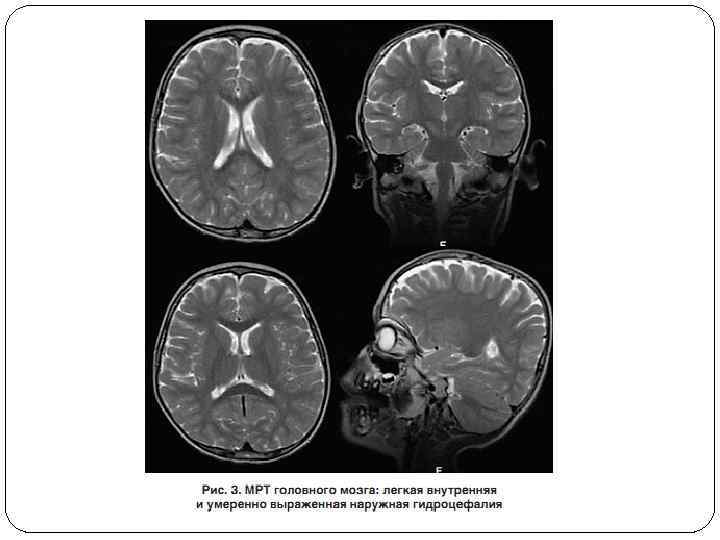

КТ и МРТ Методы компьютерной и магнитно-резонансной томографии, как правило, не дают дополнительной информации о поражении ЦНС при этом заболевании. При компьютерной томографии отмечена субатрофия коры головного мозга При магнитно-резонансная томографии: - выявляют билатеральную атрофию в лобновисочных областях коры больших полушарий - признаки атрофии мозжечка лишь на третьемчетвертом десятилетии жизни.